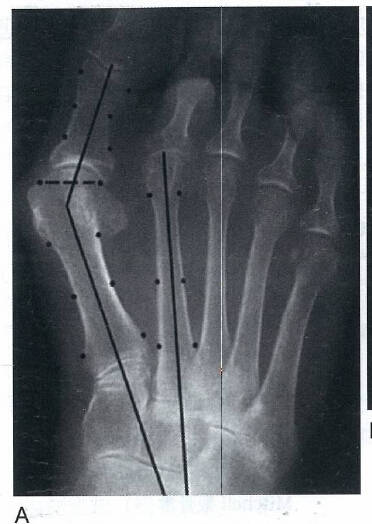

其他两个涉及第一跖趾关节的解剖学改变也可以引起拇外翻

第一个改变为跖骨头关节面偏斜,其偏斜的角度被称为跖骨远端关节固角(DMAA)

2.jpg

1.jpg

第二个改变为趾近节趾骨基底的关节角相对于其纵轴出现偏斜,其偏斜角度被称为趾骨近端关节固角(PAA)